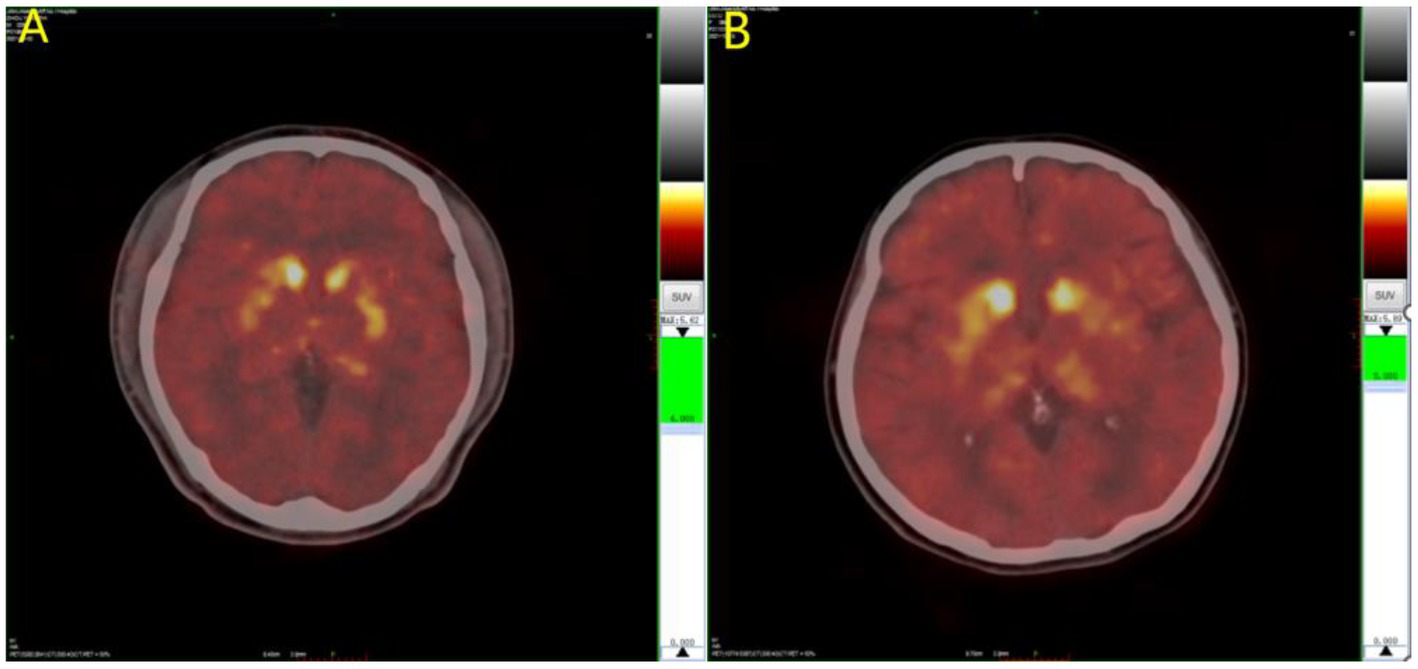

The results of the covariance analysis after correcting for disease duration showed that 11C-CFT uptake in the caudate nucleus in the EOPD group was significantly higher than in the LOPD group (t = 3.002, p = 0.003). There was no significant difference between the anterior and posterior putamen 11C-CFT uptake between the EOPD and LOPD groups (Table 2 and Figures 1, 2).

11C-CFT PET images of Parkinson’s disease. (A) LOPD; (B) EOPD. 11C-CFT PET metabolic model for EOPD and LOPD: 11C-CFT uptake in the caudate nucleus in patient with EOPD was significantly higher than LOPD, and there was no significant difference between the anterior and posterior putamen between patients with EOPD and LOPD.